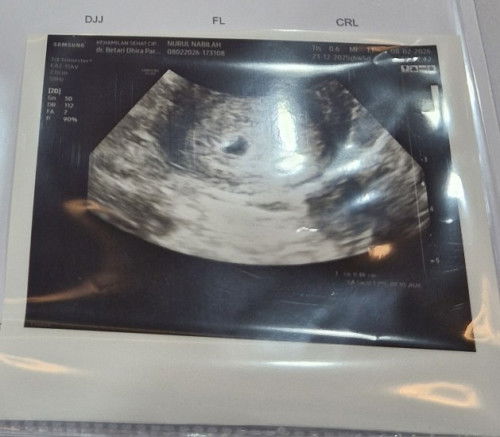

Ini usg pas hamil 5w2d baru kantong kecil normal gak ya?

Sama kak, aku jg baru USG 2 hari yg lalu. Perkiraan usia pas itu 5w2d dan baru keliatan kantong, dalemnya blm keliatan

ini usg 2 dimensi kak, tapi yg transfaginal